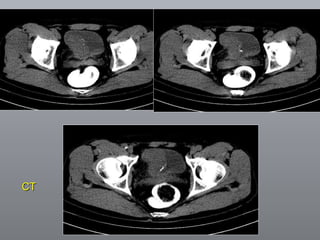

Câncer de Bexiga Estudos de imagens Diagnóstico Ultrassonografia Urografia excretora Estadiamento CT RNM Rx tórax  Cistoscopia + biópsia + biópsias randomizadas

CT